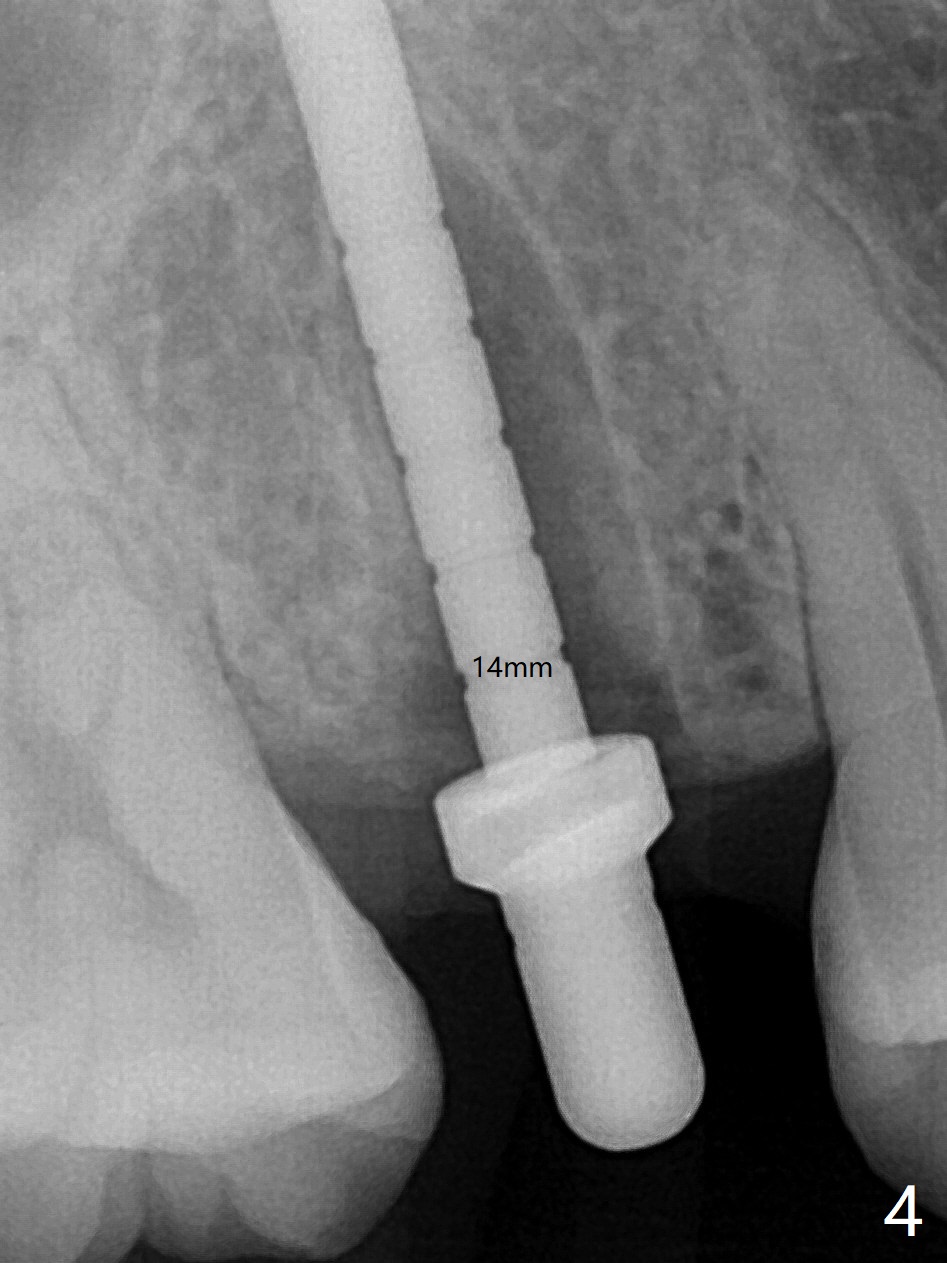

4号牙残根(图一)无创伤拔除使用一种叫做proximators牙周刀(periotomes,图二,三)。初期钻洞方位尚可(图四,五),植入3.8x15毫米植体,扭力50Ncm,修复成品基台完全就位(图六,七),植体,基台周围间隙填入骨粉(用血液调袢)后,制备基台(图八)和临时牙冠。